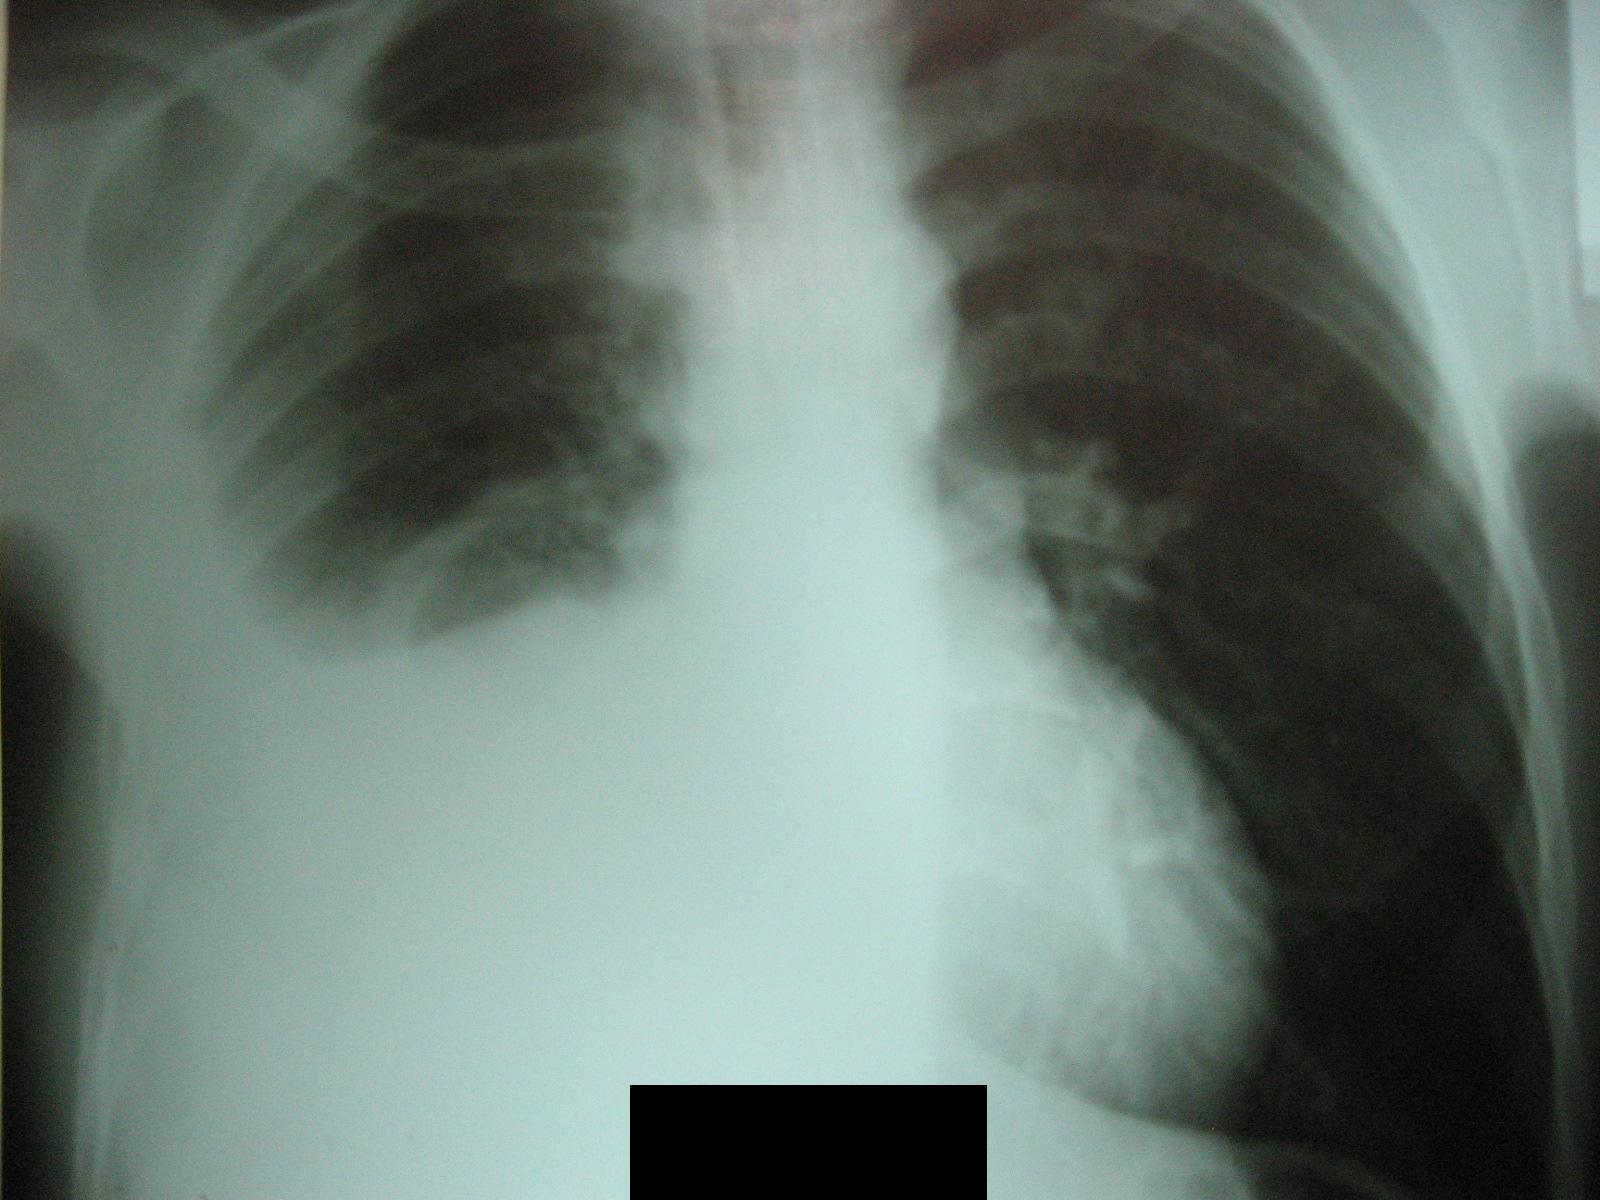

Снимок легких при туберкулезе является важным методом диагностики этого заболевания. На рентгеновских снимках можно увидеть изменения в легких, которые свойственны туберкулезу.

Рентген грудной клетки туберкулез

Рентгенография грудной клетки туберкулез

Рентгенография грудной клетки туберкулез

Рентген грудной клетки туберкулез

Рентген грудной клетки туберкулез

Фотографии снимков легких при туберкулезе

В данной статье представлены многочисленные фотографии снимков легких при туберкулезе, чтобы помочь вам понять, как выглядят изменения легких на рентгеновских снимках при этом заболевании.